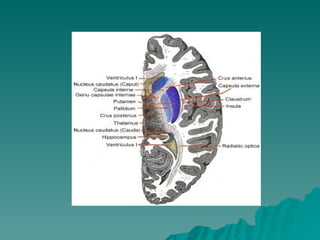

ESTRUTURA E FUNÇÃO DOS GÂNGLIOS DA BASE CLAUSTRUM CORPO AMIGDALÓIDE NÚCLEO CAUDADO PUTAMEM  ESTRIADO  LENTIFORME  GLOBO PÁLIDO ESTUDOS MAIS RECENTES Núcleo basal de Meynert Núcleo Accubens (integrante do corpo estriado ventral) ALGUNS AUTORES Substância Negra  Subtálamo

DISPOSIÇÃO  ANATÕMICA Núcleo Caudado  = Massa volumosa e alongada, relacionada  em toda sua extensão com os ventrículos laterais Cabeça  Corno Anterior Corpo  Assoalho Central Cauda  Extremidade Anterior do corno inferior A cabeça do núcleo caudado se funde com a parte anterior do núcleo lentiforme

LENTIFORME = FORMA DE UMA CASTANHA DO PARÁ Não aparece na superfície ventricular – Profundo Medialmente se relaciona com a cápsula interna  Separa do caudado e do tálamo Lateralmente  córtex da ínsula, separado pela  substância branca e pelo claustrum DIVIDIDO – Putamem = lâmina medial Globo pálido = lâmina mais lateral e branca  Coloração mais clara = fibras mielínicas que a atravessam PARTE EXTERNA GLOBO PÁLIDO  lâmina medular  medial PARTE INTERNA